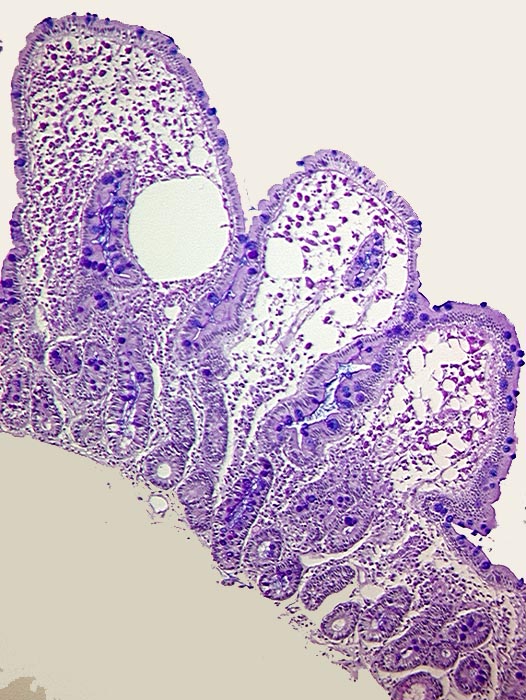

AP/ Morbus Whipple

Morbus Whipple

Dünndarm